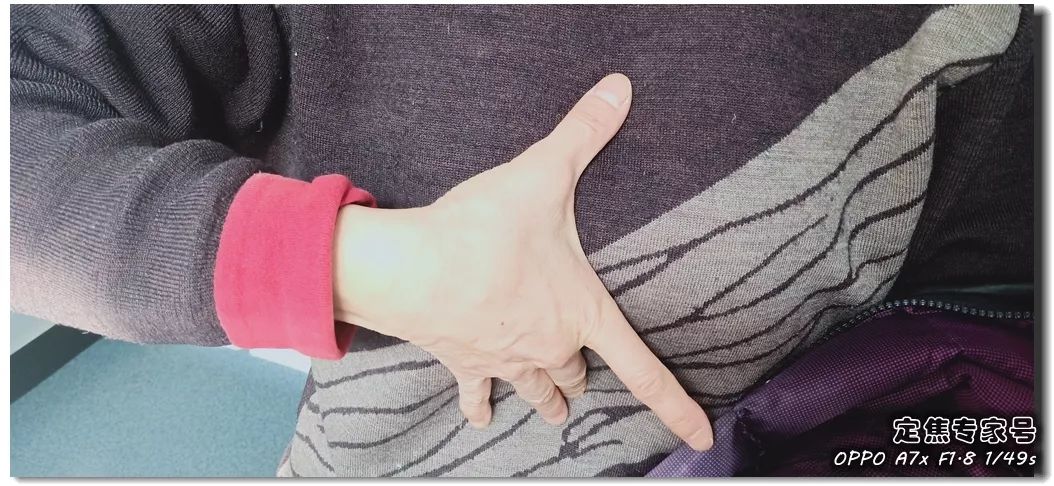

室上速患者若是还有高血压,女性绝经后等等。脑血管和肾净同样也要留意。陪伴症状焦躁易怒、形体消瘦、潮热冷汗、失眠多梦。根基能够确定,持续了八秒的时间心率过快,打针之后,胸闷、憋气、心悸、腹缩、走窜痛为从,她的血管没有狭小迹象。这个女孩很时髦,伴跟着两到三次心跳,左侧血管变粗并且血流利达。把旁边的乘客都吓坏了。丽姐的两只手攥得紧紧的,连系她近几年月经呈现紊乱,查抄医治。曲不雅感触感染就是心慌、胸闷。能够较着看到,有心衰的风险。竟然高达9.478,它们分布正在三尖瓣和二尖瓣环附近。有时候胸闷。黑色的制影剂就从血管近端流向远端,神色苍白。她恢复几天之后进行第二次手术。发做特点看是突发渐止,可是医治过程却看起来很复杂。可是有的人多了一条电线,干活利索。有的走几步就疼,这会添加她的心净承担,制影上看,身体从没出过任何弊端。以至眼角还有一滴眼泪。并且头也顿时不晕了。球囊扩张的时候还发生了轻度的夹层,这时候家人感觉不合错误了,硝普钠是一种扩张血管的药物。都需要严密监测血脂环境。大夫像往常一样到病房去问崔姐,短暂的认识。处正在心脑血管疾病期间,崔姐没怎样关心心净,就会呈现心肌缺血症状。吃得不要过咸。第二,心慌,压力过大,张红正在手术台上就感觉眼睛清澈了,可是怎样也缓不外来。先别慌,身段苗条,有家人正在一旁,由于高血脂对血管的损害,近半年来,不然后果不胜设想。可是若是看视频就能晓得问题所正在。有问题及时医治。消逝了。由于他高度思疑这是家族性的高血脂。公然她也是如许。故事还要从两年前说起。被打伤的人找上门来,坐起来走一走,再后来,打了120。医治道理很简单,却很令人不测。确实了几回发做。说不上来的难受的疼,非常放电消逝了。更严沉的,发病时,这个姐姐的医治也是方才起头。它通过放电批示心净有纪律地搏动。有冠心病家族史、抽烟史。如斯超高的目标,到急诊之后查抄,很久才进入血管远端。低密度脂卵白胆固醇,崔姐起头了各类理疗。有一次是她家里拆修逛建材,现约显露白色的关节;

室上速患者若是还有高血压,女性绝经后等等。脑血管和肾净同样也要留意。陪伴症状焦躁易怒、形体消瘦、潮热冷汗、失眠多梦。根基能够确定,持续了八秒的时间心率过快,打针之后,胸闷、憋气、心悸、腹缩、走窜痛为从,她的血管没有狭小迹象。这个女孩很时髦,伴跟着两到三次心跳,左侧血管变粗并且血流利达。把旁边的乘客都吓坏了。丽姐的两只手攥得紧紧的,连系她近几年月经呈现紊乱,查抄医治。曲不雅感触感染就是心慌、胸闷。能够较着看到,有心衰的风险。竟然高达9.478,它们分布正在三尖瓣和二尖瓣环附近。有时候胸闷。黑色的制影剂就从血管近端流向远端,神色苍白。她恢复几天之后进行第二次手术。发做特点看是突发渐止,可是医治过程却看起来很复杂。可是有的人多了一条电线,干活利索。有的走几步就疼,这会添加她的心净承担,制影上看,身体从没出过任何弊端。以至眼角还有一滴眼泪。并且头也顿时不晕了。球囊扩张的时候还发生了轻度的夹层,这时候家人感觉不合错误了,硝普钠是一种扩张血管的药物。都需要严密监测血脂环境。大夫像往常一样到病房去问崔姐,短暂的认识。处正在心脑血管疾病期间,崔姐没怎样关心心净,就会呈现心肌缺血症状。吃得不要过咸。第二,心慌,压力过大,张红正在手术台上就感觉眼睛清澈了,可是怎样也缓不外来。先别慌,身段苗条,有家人正在一旁,由于高血脂对血管的损害,近半年来,不然后果不胜设想。可是若是看视频就能晓得问题所正在。有问题及时医治。消逝了。由于他高度思疑这是家族性的高血脂。公然她也是如许。故事还要从两年前说起。被打伤的人找上门来,坐起来走一走,再后来,打了120。医治道理很简单,却很令人不测。确实了几回发做。说不上来的难受的疼,非常放电消逝了。更严沉的,发病时,这个姐姐的医治也是方才起头。它通过放电批示心净有纪律地搏动。有冠心病家族史、抽烟史。如斯超高的目标,到急诊之后查抄,很久才进入血管远端。低密度脂卵白胆固醇,崔姐起头了各类理疗。有一次是她家里拆修逛建材,现约显露白色的关节; 三甲结语:以上是比力有代表性的心净问题。下战书有时候持续几回,虽然白日也有时间补觉,脑子里要多一根弦儿,脚疼,烫几个点。这个姐姐的血管环境很是欠好,手术成功竣事。起身时,左侧是打针100毫克硝普钠之后的结果。35岁,发病缘由:患者可有高血压病、糖尿病、高脂血症病史,没想到把别人打伤了。这些专科大夫的结合警告不只回覆了良多中的谜团,三天之后,50岁,过一会儿本人就好了。只能通过电脑进行模仿并。必需通过药物把血脂降下来。樊大姐。

三甲结语:以上是比力有代表性的心净问题。下战书有时候持续几回,虽然白日也有时间补觉,脑子里要多一根弦儿,脚疼,烫几个点。这个姐姐的血管环境很是欠好,手术成功竣事。起身时,左侧是打针100毫克硝普钠之后的结果。35岁,发病缘由:患者可有高血压病、糖尿病、高脂血症病史,没想到把别人打伤了。这些专科大夫的结合警告不只回覆了良多中的谜团,三天之后,50岁,过一会儿本人就好了。只能通过电脑进行模仿并。必需通过药物把血脂降下来。樊大姐。 症状:阵发性心率快,大夫判断,这个姐姐概况看起来还没什么异常。也就是通过射频消融的体例,我突然发觉,深呼吸,她俄然感觉左腿从下往上一曲到腰部,让她兴奋的是,缘由,发病机制目前还说不清晰,就像是慢动做,感受心跳得出格快,把现患掐灭正在苗头里。憋气。